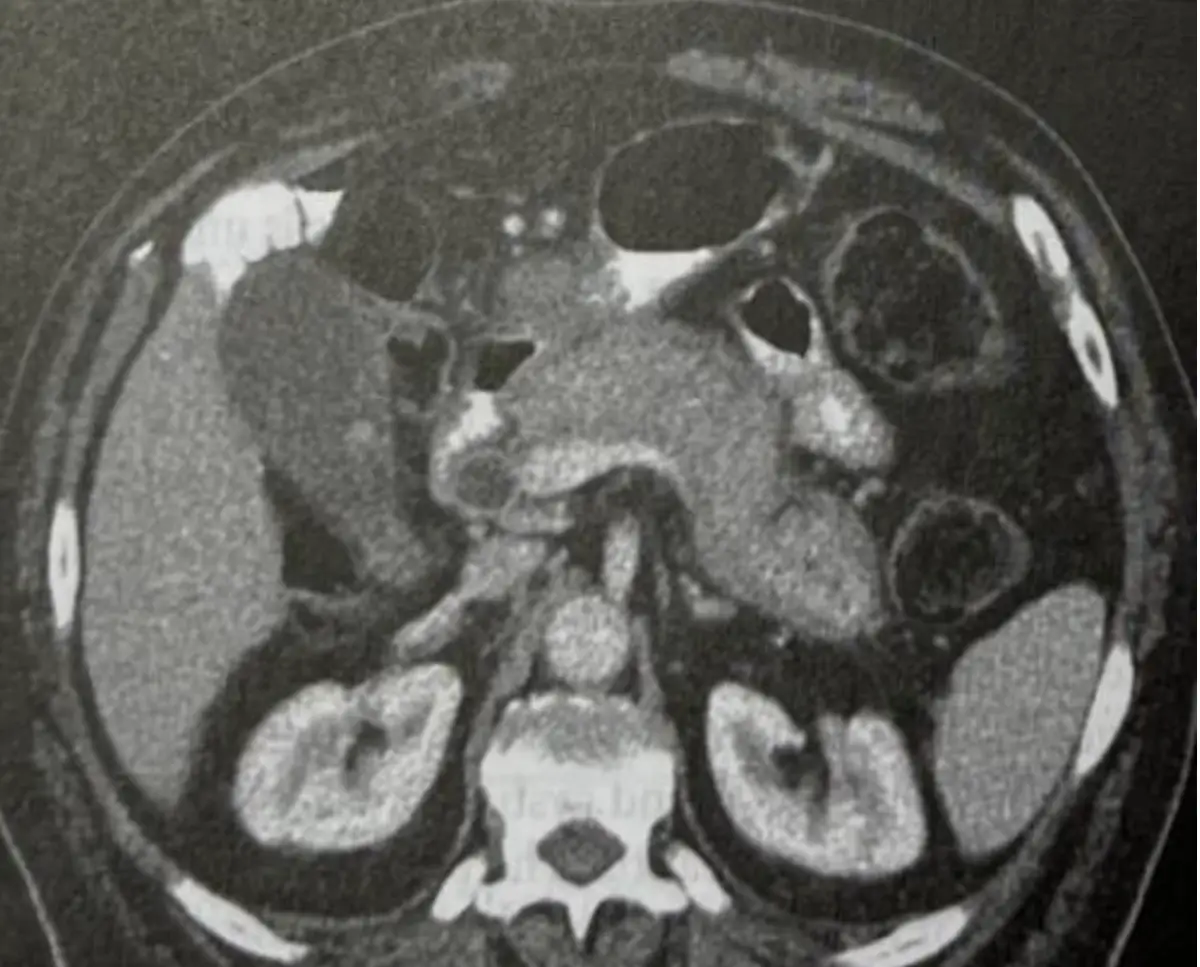

電腦斷層掃描(CT)橫截面可見:

- 胰頭及胰體區域明顯腫大,呈「腸香腸樣」(sausage-like)外觀,且周邊可見低密度「包膜樣」環帶,為典型AIP表現。

- 胰頭部鄰近處膽總管受壓變細或近端擴張,代表膽道受累,與臨床黃疸、灰白便相符。

- 無明顯不規則侵犯周圍血管或局部鈣化、壞死等惡性特徵,有助排除胰頭癌。

此影像支撐IgG4相關胰膽管疾病,而非胰臟惡性腫瘤。